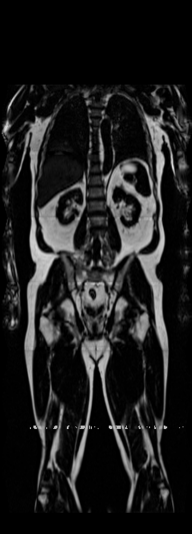

Notably, X-Diffusion achieves state-of-the-art dB for a few input slices while baselines require more than 60 input slices to achieve similar performance (Figure 7). The margin is more than 12 dB PSNR for the 1-slice input in both the BRATS and the UK Biobank benchmarks (see Table 1 and Figure 6). For reference, two randomly sampled MRIs from UK Biobank would have a PSNR of 15.95 dB 0.36 (on 4800 randomly sampled examples). Omitting the preprocessing step of alignment DXA to MRI, leads to a drop of PSNR on average by 2.87 dB (29.01 dB 26.14 dB). The slices from 3D reconstructed volumes at varying depths and axis of rotation, visually match the ground truths for both brain and whole-body scans (see Figures 4 and 5 left). We also plot the error map (Figure 3) and the spread of the error (Figure 5 right) of such X-Diffusion generations to highlight the differences with the ground truth MRIs.

Preservation of Spine Curvature. For the spine segmentation on UK Biobank, we use a UNet++ model [83] with Dice Loss. We use a model trained to predict curves on DXA on UK Biobank [11]). We measure the Pearson correlation factor [11] of spine curvature measured on the generated MRIs where the input is a single MRI coronal slice, a single sagittal slice, or from the paired DXA, against the curvature of reference real MRIs of the same samples. The correlation coefficients are 0.89 for the coronal MRIs, 0.88 for the sagittal MRIs, and 0.87 for the DXAs on the test set of 308 human-annotated angles. We can then bin the curvature of the spines under different scoliosis categories based on human-annotated angles: mild: , moderate: , and severe . We show the results in Figure 8. This illustrates that the generated MRIs preserve the spine curvature from normal to severe scoliosis cases. Additional details about spine curvature are provided in supplementary material.